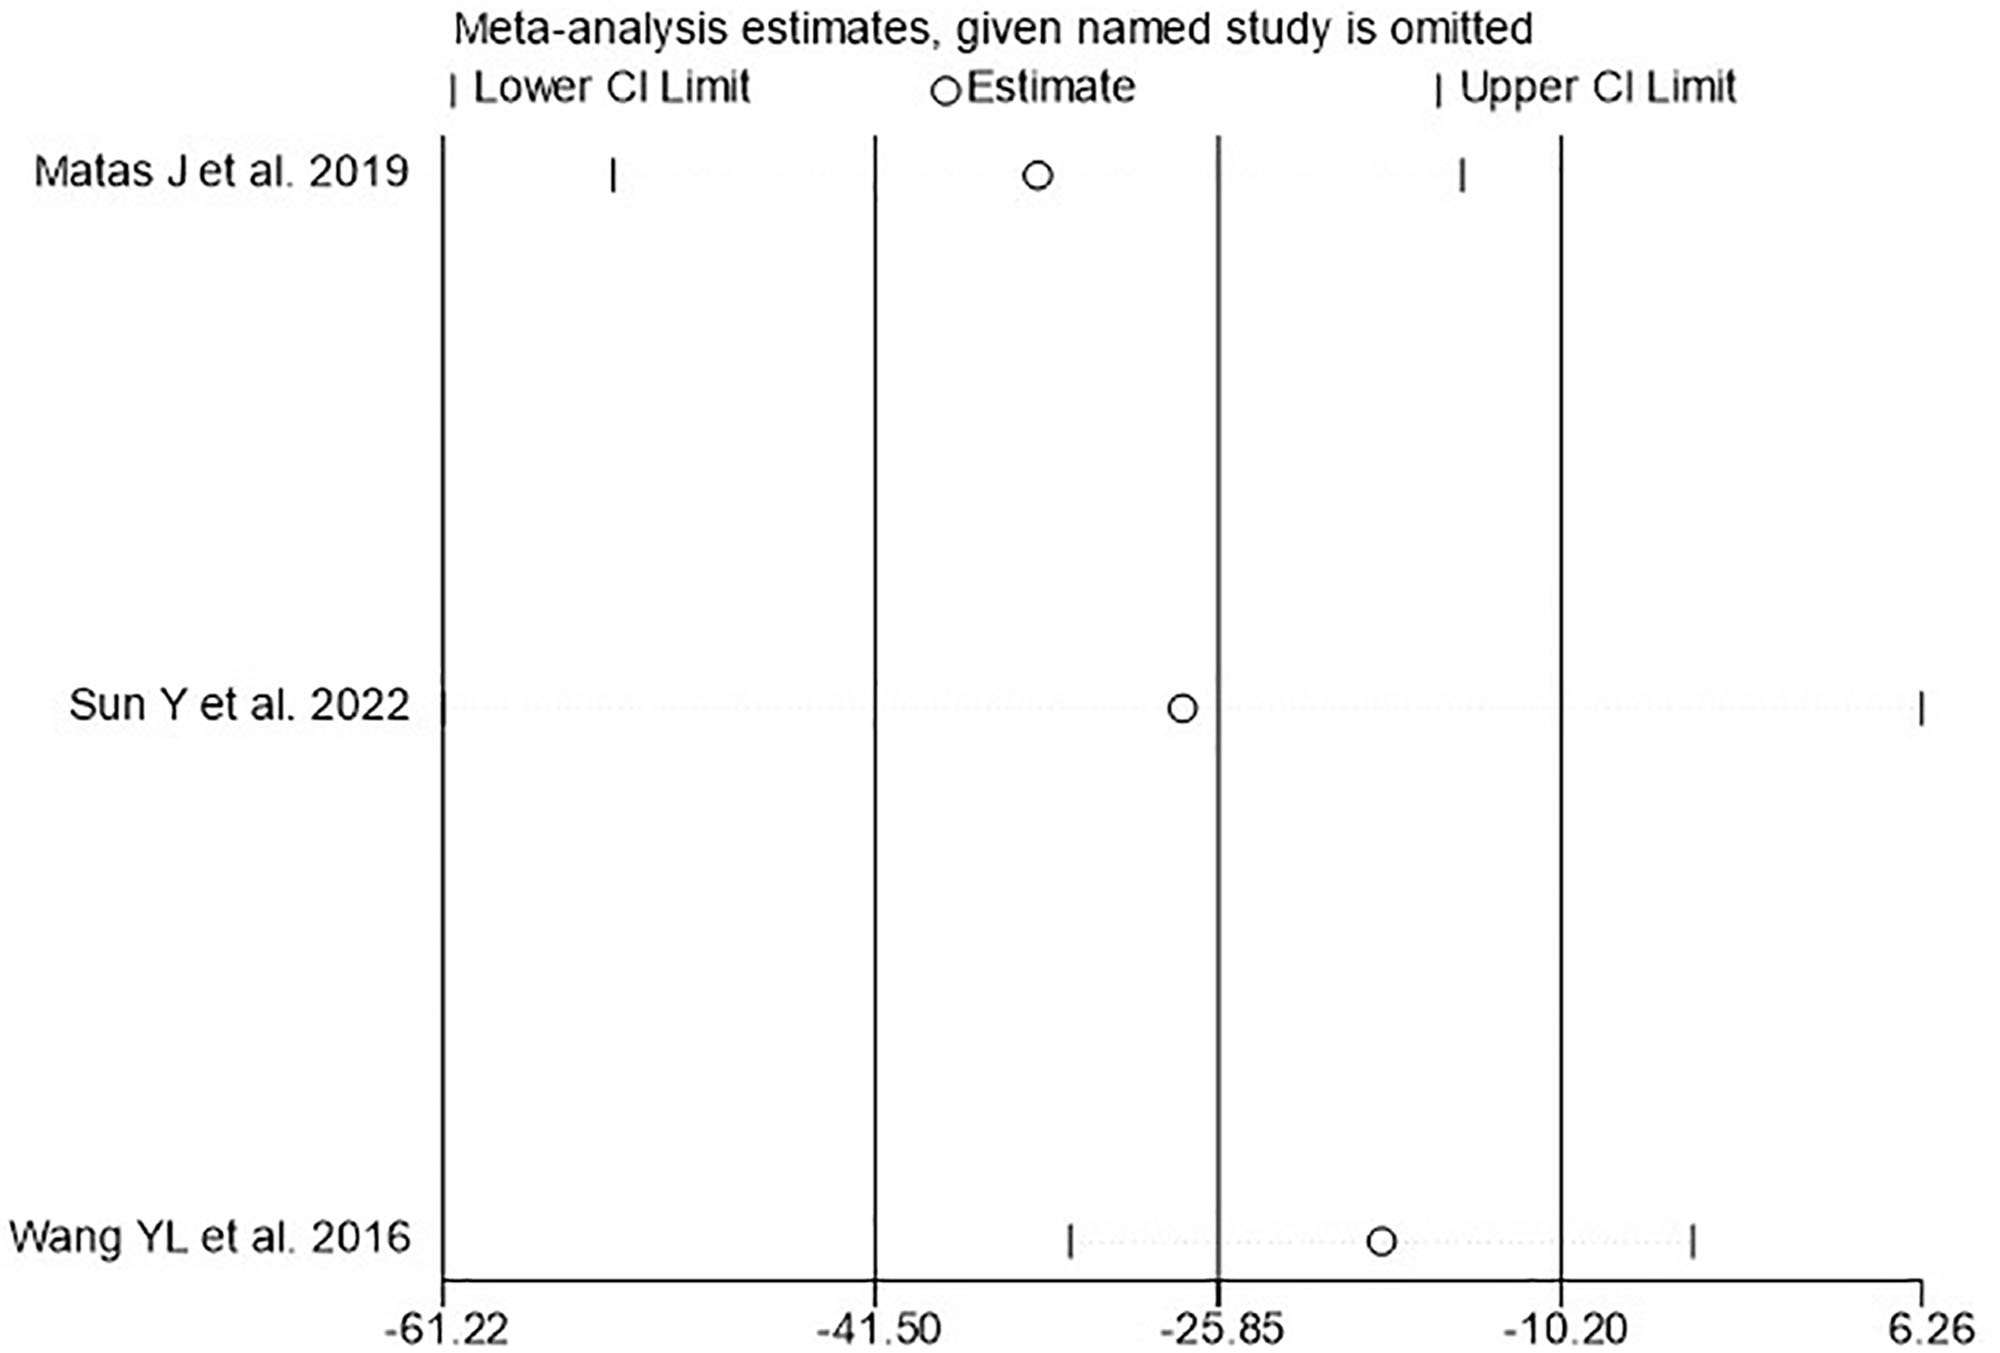

敏感性分析:WOMAC薈萃分析結(jié)果顯示異質(zhì)性較高,且納入研究數(shù)量較少,無法進(jìn)行亞組分析,因此進(jìn)行了敏感性分析,結(jié)果顯示,單獨(dú)排除文獻(xiàn)后,結(jié)果仍在95%CI內(nèi),表明結(jié)果穩(wěn)定(圖7)。

WOMAC=西安大略和麥克馬斯特大學(xué)骨關(guān)節(jié)炎指數(shù)。

討論:本研究納入3個(gè)試驗(yàn),分析臍帶間充質(zhì)干細(xì)胞治療膝骨關(guān)節(jié)炎的療效。Meta分析顯示,接受臍帶間充質(zhì)干細(xì)胞治療膝骨關(guān)節(jié)炎的患者的WOMAC和KLS均較對(duì)照組有明顯改善,提示臍帶間充質(zhì)干細(xì)胞可以改善膝骨關(guān)節(jié)炎的功能和疼痛。Egger檢驗(yàn)提示無出版偏倚。但WOMAC結(jié)果存在異質(zhì)性,敏感性分析提示結(jié)果穩(wěn)定,因此異質(zhì)性高可能與納入研究數(shù)量少或樣本量不足有關(guān)。